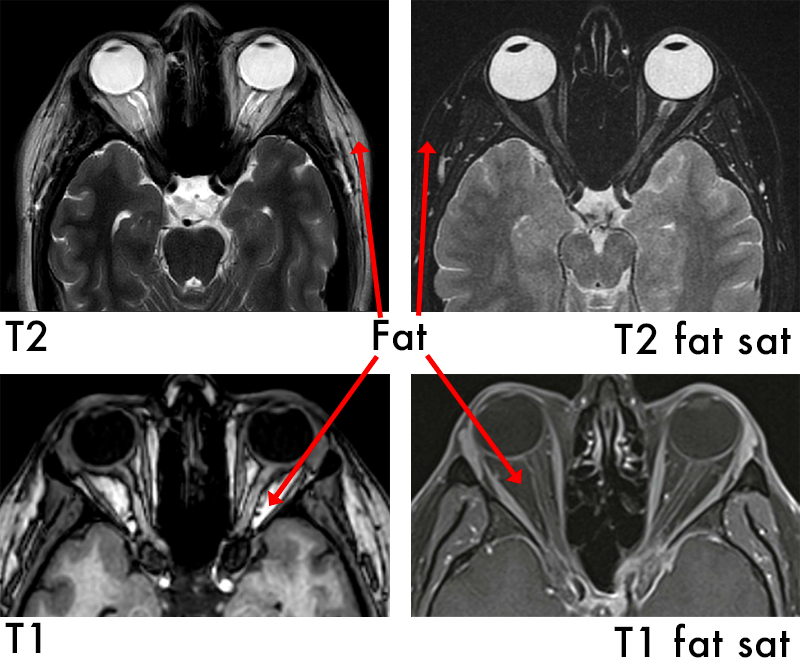

T1 Weighted Imaging

T1 is typically used as an informal anatomy scan.

Fat is Bright (quickly realigns its longitudinal magnetisation with B0)

Water is Dark (has much slower longitudinal magnetisation realignment after an RF pulse and therefore, has less transverse magnetisation)

Applications:

T1 focuses on highlighting anatomy

Useful to detect contrast

As contrast media goes to areas of high blood supply it can detect infections

T2 Weighted Imaging

T2 is good for detecting pathologies such as cysts

Water is bright

Fat is grey

Applications:

T2 focuses on pathology, making fluids bright, which is ideal for visualizing inflammation, edema, and certain lesions

T2 Fat Saturation

T2 Fat Saturation is used to see inflammation. This technique “turns off” or removes any fat from the image so now:

Fluid is bright

Bone is dark

Fat is dark

Applications:

Enhance the visualization of specific tissues or structures by suppressing the signal from fat